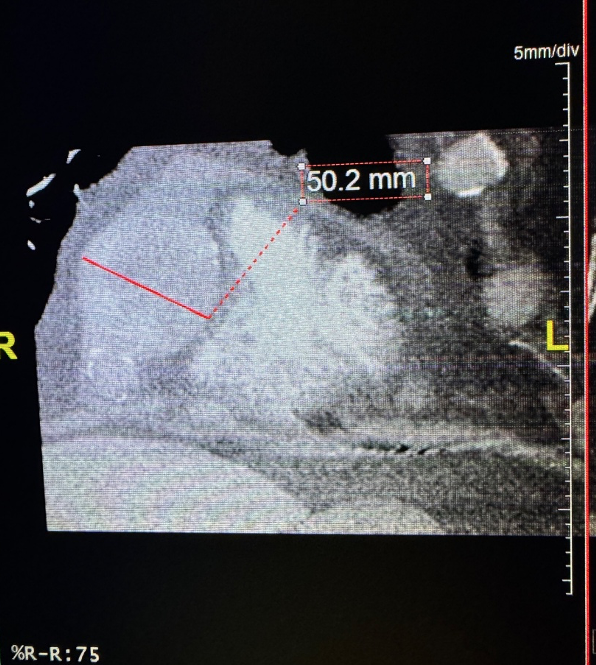

Subsequently, coronary CT angiography was performed, showing the exact sizing of the aneurysms and patency of the distal vessel, and confirming the multivessel giant coronary aneurysms diagnosis (Figures 4-6). A cardiothoracic surgery opinion was obtained, but no surgical options would be of benefit per surgical service, since there was no obstructive disease. The patient’s underlying cardiomyopathy was likely due to chronic micro thrombo-embolic phenomena from the coronary aneurysms. It was determined that the patient would be best treated with long-term oral anticoagulation and GDMT for heart failure.